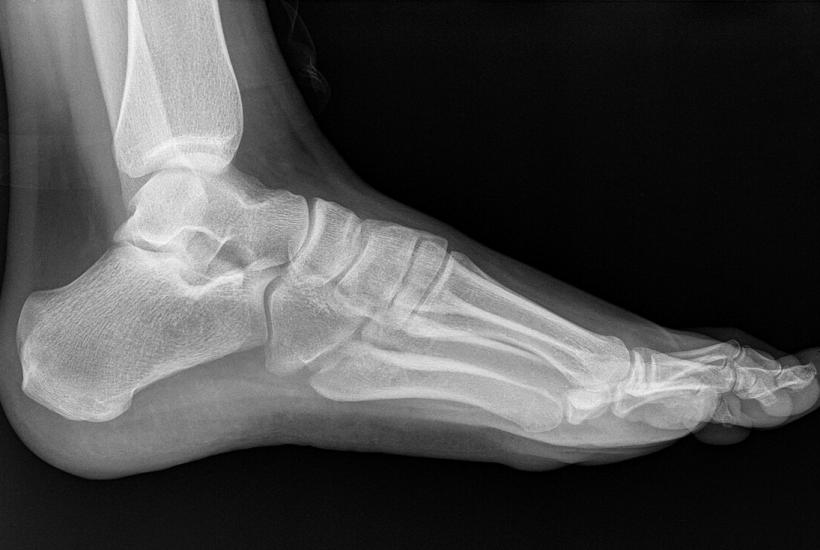

Поначалу заболевание проявляется болью в пятке, особенно утром или после отдыха. Без лечения воспаление может привести к образованию костного нароста — пяточной шпоры, которая потребует хирургического вмешательства.

Плантарный фасциит также подошвенный фасциоз или пяточная шпора - это заболевание, обусловленное воспалительно-дегенеративными изменениями плантарной (подошвенной) фасции.